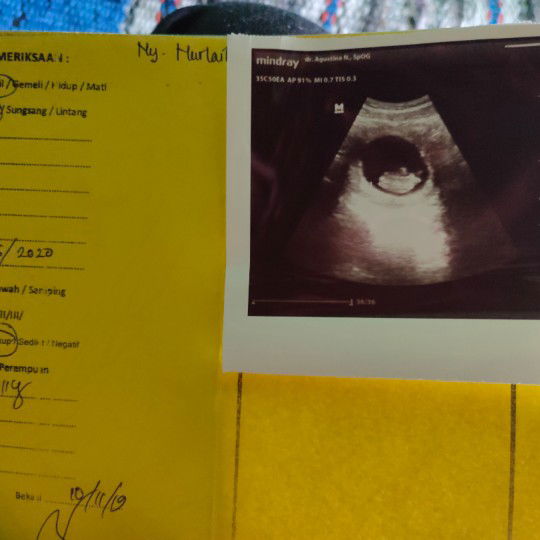

tentang USG

Assalamualaikum bunda.. Ini hasil usg pertamaku dan anak pertamaku. Sempet khawatir berlebihan kalau habis liat postingan tentang hamil BO. Alhamdulillah pas usg aku lega bun, dede utunnya ada. ? Alhamdulillah semua baik, air ketubannya juga banyak kata dokternya. Oh iya bun, pas usg dedenya nongolin bagian kepala ajah bun, ga melintang. Padahal aku mau liat dede bentuknya sempurna. Ada yg sama kaya aku ga bun? Usg pertama tapi bagian kepala yg ke raba mesin usg nya